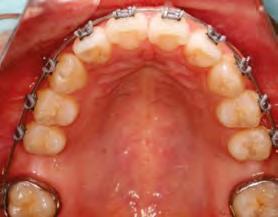

en paciente adulto tratado con extracciones de primeros molares permanentes. Reporte de caso

Dentista y Paciente 52 Sonriendo al futuro